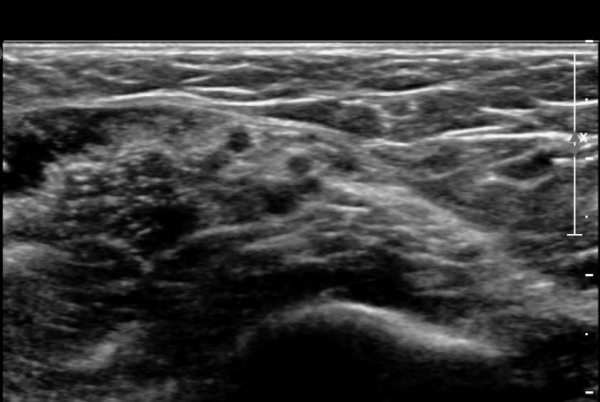

¾Æ·§ÆÈ¿¡¼­ Àü°ñ°£ ½Å°æºÎÀ§ Ⱦ´Ü¸é°Ë»ç»ó ¾öÁö ±¼±ÙÀÇ °í¿¡ÄÚ º¯¼ºÀÌ °üÂûµÇ°í  Àü°ñ°£µ¿¸Æ

ÁÖÀ§¿¡¼­ Á¾±« µî Ưº°ÇÑ ÀÌ»ó ¼Ò°ßÀÌ °üÂûµÇÁö ¾Ê´Â´Ù(»çÁø 1).